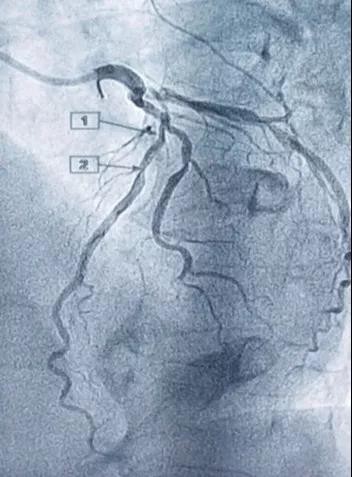

今年71岁的男性患者,有冠心病病史,因近3天无诱因出现胸痛、胸闷到德宏友谊医院就诊,经行冠状动脉造影术显示:患者冠脉病变堵塞严重,冠状动脉粥样硬化性心脏病LM远端狭窄60%,LAD近中段弥漫性病变,最狭窄处75%,D1开口处狭窄60%,患者情况十分危急。经与患者家人沟通,立即行冠状动脉支架植入术,成功在病变处植入支架,支架植入后血管再通效果良好,患者术中状态良好,术后胸闷症状有明显改善。